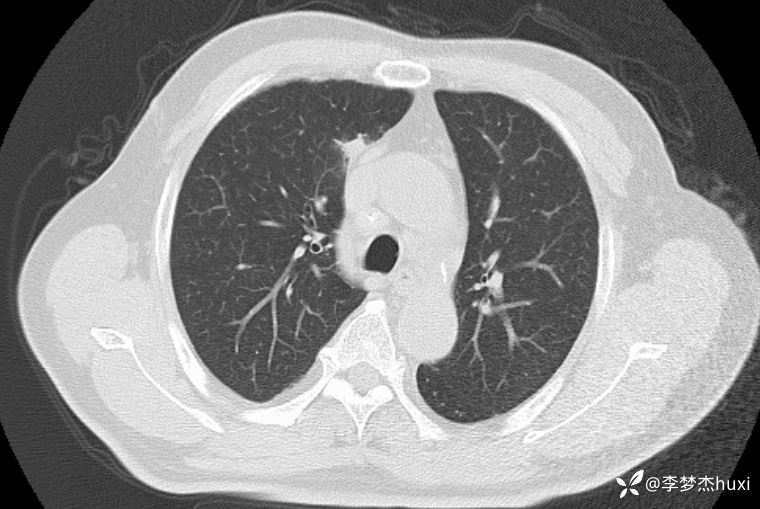

男性63岁,热伴胸痛4天,胸部CT示双肺多发结节,考虑什么疾病?

【现病史及既往史】: 1.患者老年 男,患者于入院前4天无明显诱因出现发热,具体体温不详,伴右侧胸痛,无放射痛,偶有咳嗽、无明显咳痰,无鼻塞,无咽痛,无胸闷、憋气,无恶心、呕吐,无腹痛、腹泻,无尿急、尿频、尿痛,院外口服退热药物治疗(具体不详),症状好转,今患者及家属为进一步诊治前来我院就诊,门诊查胸部CT:双肺炎症;双肺间质性改变;右肺上叶肺大疱?纵隔内肿大淋巴结,部分钙化;主动脉及冠状动脉壁钙化;双侧胸膜局部增厚;右侧第9、10肋骨欠规整?;右侧胸壁术后改变,双肺实性结节,建议复查或肺结节门诊检查,故门诊以“社区获得性肺炎,非重症”收入院。

【临床诊断】: 社区获得性肺炎,非重症。